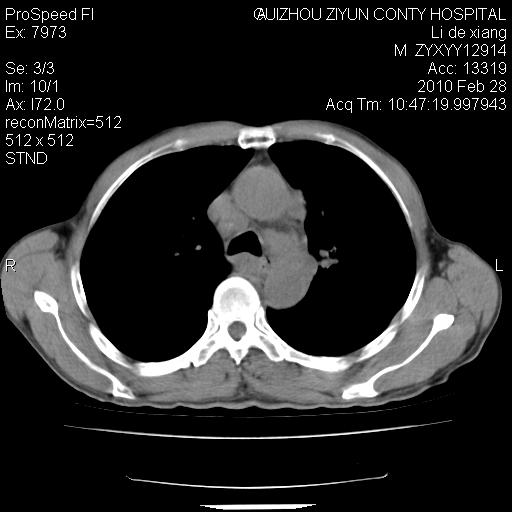

标题: CT24776:男 71Y 咳嗽咳痰胸痛两月,伴声音嘶哑。 [打印本页]

纵膈淋巴结肿大 不除外占位性阻塞

左侧中央型肺癌伴左肺上叶阻塞性肺炎及节段性不张可能性大,建议纤支镜检查!纵隔淋巴结转移.

左侧中央型肺癌伴左肺上叶阻塞性肺炎及纵隔淋巴结转移。

左上叶支气管狭窄,阻塞性病变,肺门肿块,纵隔及肺门淋巴结增大,中央性肺癌

左肺中央型肺癌并阻塞性改变、纵膈 淋巴结转移